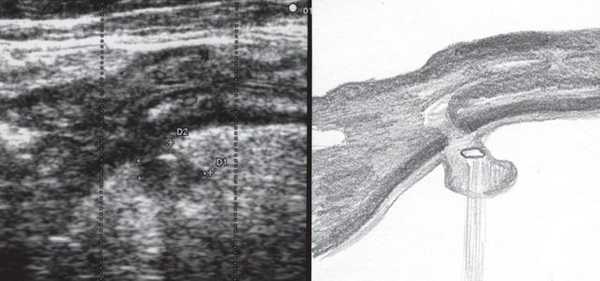

К задней стенке культи шейки матки прилежит участок прямой кишки толщиной до 2,9 см на протяжении до 7,4 см. Стенка кишки неравномерно утолщена до 0,5-0,6 см, пониженной эхогенности, дифференцировать слои стенки не представляется возможным. При ультразвуковой ангиографии на измененном участке определяется выраженная васкуляризация с наличием сосудов с артериальным типом спектра (Vmax 14,4 см/с, RI 0,74). Перистальтика кишечника в данном сегменте отсутствует, внутренний просвет не дифференцируется. Слева от описываемого участка кишечника в межкишечном пространстве определяется гипоэхогенное образование с четкими ровными контурами, неоднородной структуры, размером 2,6х1,9х2,3 см. При ультразвуковой ангиографии в нем лоцируются множественные деформированные сосуды (рис. 1, а, б, в).

а) В-режим.

В полости малого таза, кзади от культи матки, определяется участок кишечника размером до 6,8х2,9х7,4 см с утолщенной до 0,5-0,6 см стенкой сниженной эхогенности. Перистальтика кишечника в данной проекции отсутствует, внутренний просвет дифференцируется нечетко. Содержимое кишечника практически не определяется, просвет сомкнут.